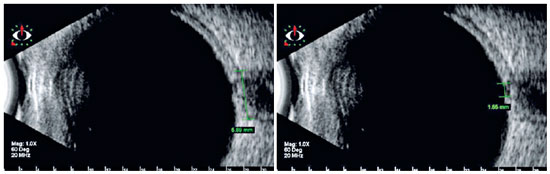

Ultrasonography

Ultrasonography has been widely used in investigations related to the diameter and, contiguously, sheath of the retrobulbar optic nerve in glaucomatous optic neuropathy(41-43). Reduced sectional dimensions in patients with glaucoma as compared with healthy individuals were attributed to the loss of nerve fibers that occurs in this disease. It is a noninvasive and easily accessible method, which can be used to investigate the disease, especially in cases where the morphology of the optic disc does not allow a conclusive diagnosis or in the presence of opaque media, which makes visualization of the optic nerve head difficult or even impossible(42,43). Figure 3 illustrates an example of an optic nerve head observed on ultrasonography.